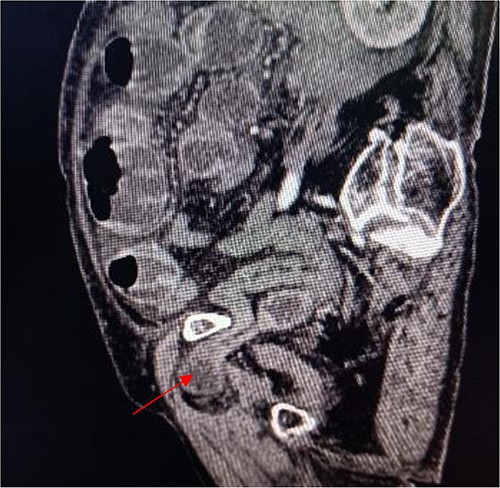

Sagittal view shows a right obturator hernia (indicated by red arrow).